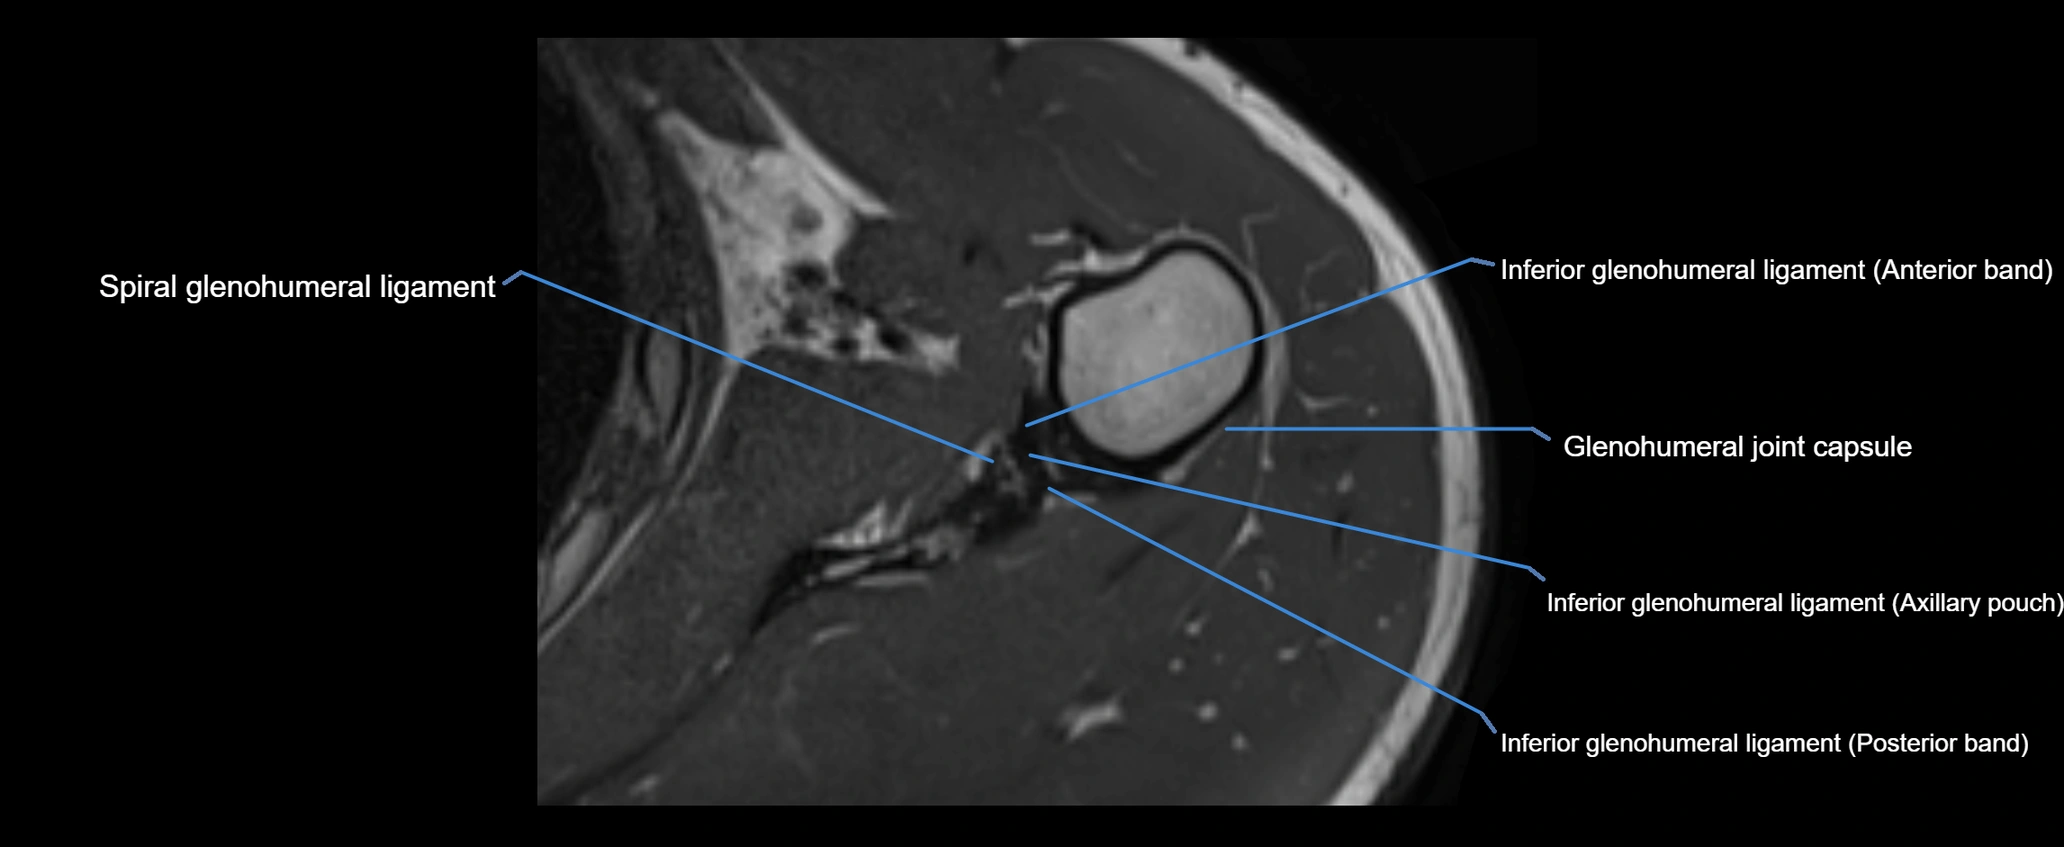

MRI Appearance

• T2-weighted images:

• Normal ligament: Low signal, homogeneous.

• Partial tear or sprain: Focal hyperintensity or thickening.

• Complete tear: Discontinuity with fluid-bright gap between clavicle and acromion.

• Associated edema: Bright signal in distal clavicle or acromion marrow.

• Proton Density Fat-Saturated (PD FS):

• Normal ligament: Low signal, uniform thickness.

• Partial tear or sprain: Bright signal or contour irregularity.

• Complete tear: Clear discontinuity with bright signal gap and joint effusion.

• Excellent for assessing joint capsule, coracoclavicular ligaments, and periarticular edema.

MRI images

image